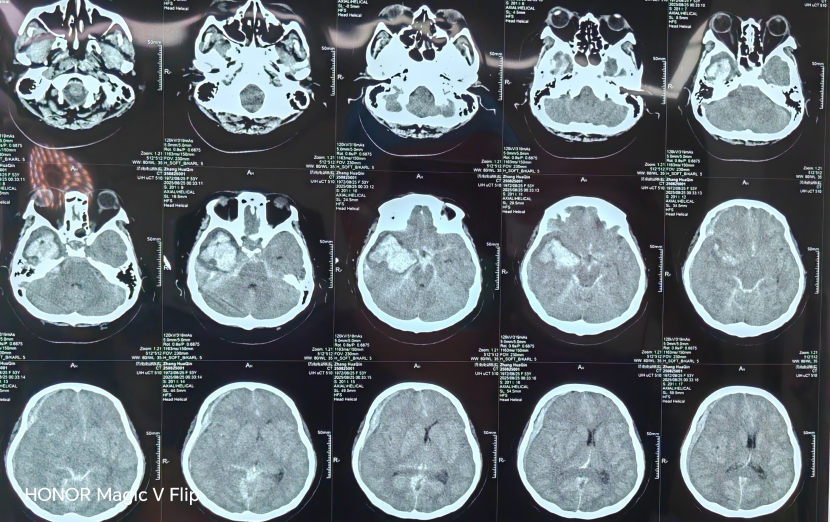

患者被送至济南南郊医院脑病科时,已处于深度昏迷状态,呼吸、心跳等生命体征极不平稳,随时可能停止。检查发现,其脑动脉瘤破裂后出血量巨大,形成的血肿已导致脑组织移位,压迫到维持心跳、呼吸的生命中枢——这是典型的脑疝表现,死亡率极高。

抢救这样的病人,对医疗团队是极大的考验。郭晓宾主任将这场手术比喻为一台“拆雷+排雷”的复合手术:不仅要清除占据空间、压迫大脑的巨大血肿(排雷),还要在视野不清、操作空间极其有限的情况下,精准找到那个随时可能再次破裂的动脉瘤,并成功将其夹闭(拆雷)。整个过程技术要求极高,容不得半点差错。